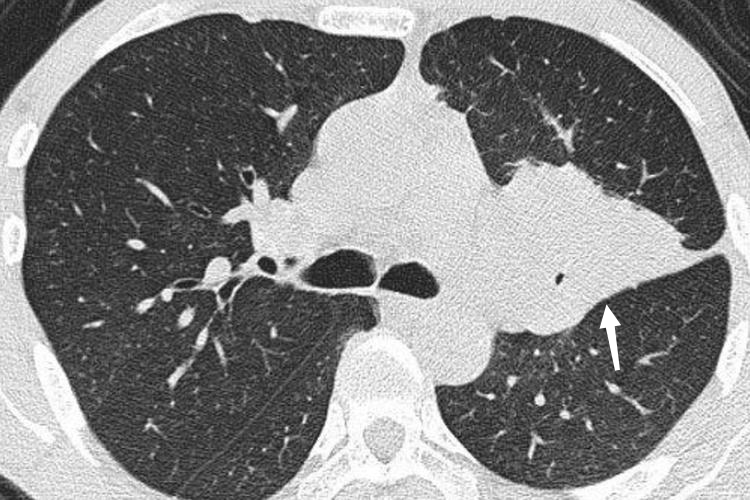

周围型:周围型肺癌CT可表现为磨玻璃结节或实性结节。